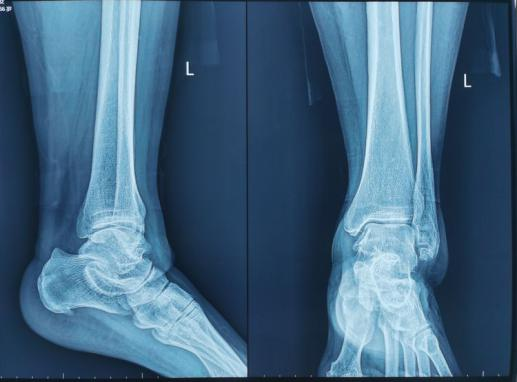

左踝關節退變,骨性關節炎,骨贅增生,踝關節無內外翻。

踝關節退變,內外側骨贅形成,軟骨破壞,關節間隙變窄。

左側踝關節鏡下可見大量炎性滑膜組織增生,骨贅生成,給予徹底清除。